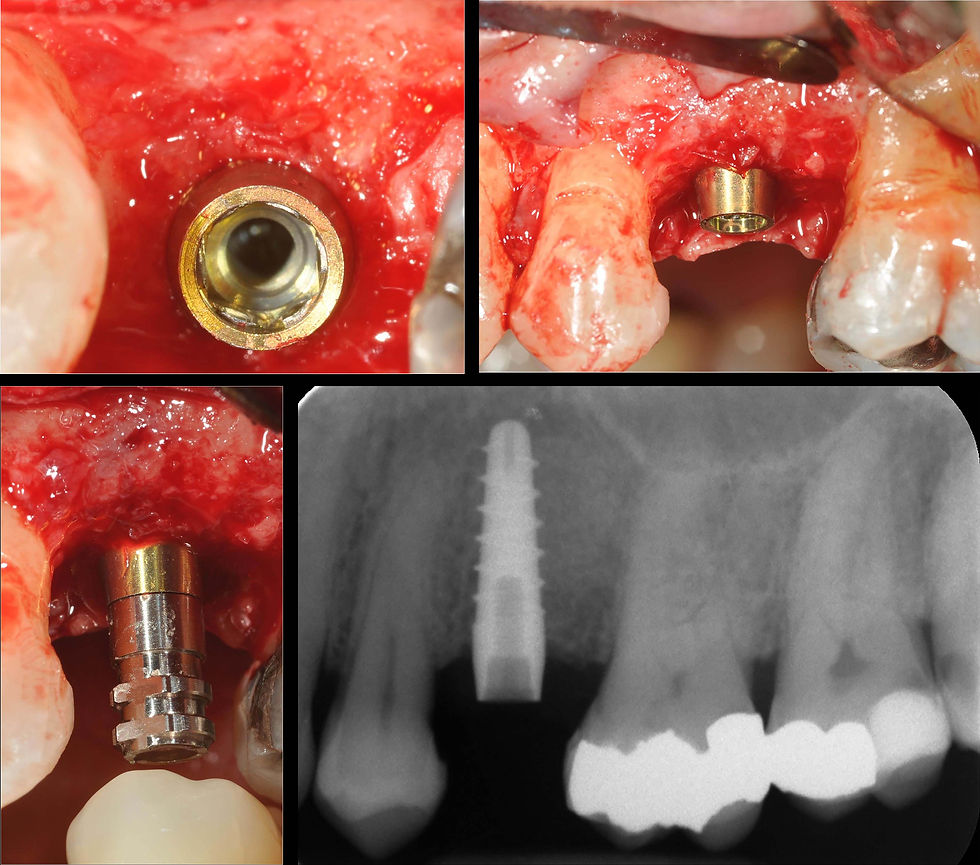

Clinical and radiographic images of the placement of the Prama RF implant, submerged up to the cylindrical portion of the convergent neck.